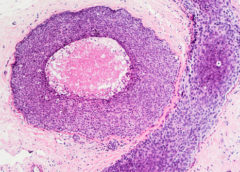

LeggiTumore mammario: test genetici mancano metà delle donne a rischio

Quasi la metà delle pazienti con tumore mammaio che ai test multigenetici presentano una variante patogena o verosimilmente patogena non corrisponde alle caratteristiche attualmente richieste per i test genetici dalle linee guida NCCN. Questo dato è emerso dall’osservazione di un campione di 959 pazienti…

LeggiTumore ovarico: metilazione BRCA1 predice responsività al rucaparib

Le cellule di carcinoma ovarico che presentano metilazione di tutte le copie di BRCA1 hanno maggiori probabilità di risposdere al PARP-inibitore noto come rucaparib. Lo suggerisce uno studio condotto su 17 pazienti da Clare Scott del The Walter and Eliza Hall Institute of Medical…